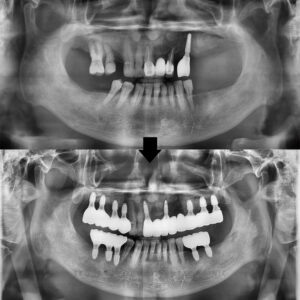

25.08.22 / 26.01.16

치료 전후 사진입니다.

환자분께서는 오래전 치료 받았던 앞니가

심미적으로 보기 싫었지만

치료 후에는 자연스러운 치아 형태와

밝아진 인상에 대해 만족해 주셨습니다.

또한 전부 임플란트로 치료하지 않고,

상태에 따라 꼭 필요한 부위만

임플란트를 진행한 점에 대해서도

만족감을 표현해 주셨습니다.

자연치아를 보존하면서

기능과 심미성을 함께 회복한 치료 계획에

신뢰를 느끼셨다고 말씀해 주셨으며,

부담을 줄이면서도 결과에

만족할 수 있었다는 점을

긍정적으로 평가해 주셨습니다.